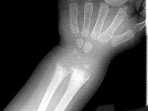

男,2岁,关节肿胀,结合图像,最可能的诊断是()

• A.肾性骨病

• B.黏多糖贮积症

• C.维生素D缺乏症

• D.维生素C缺乏症

• E.维生素D过多症